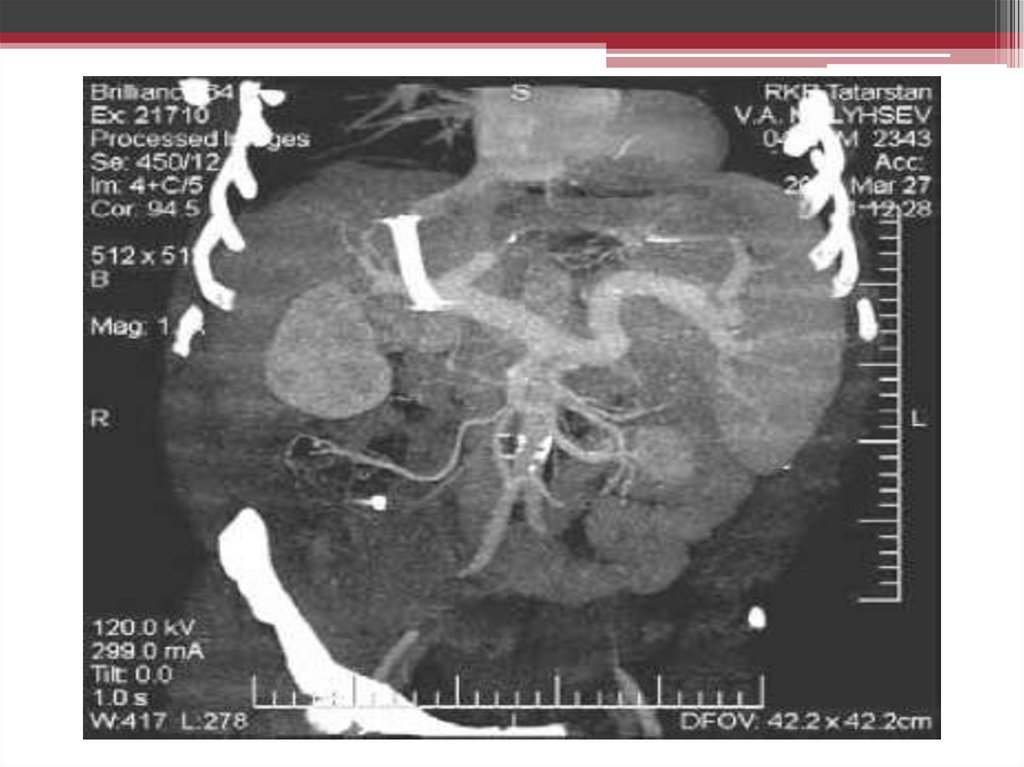

Портография с использованием

СО2(карбоксипортография)

11.

Трансъюгулярная портография